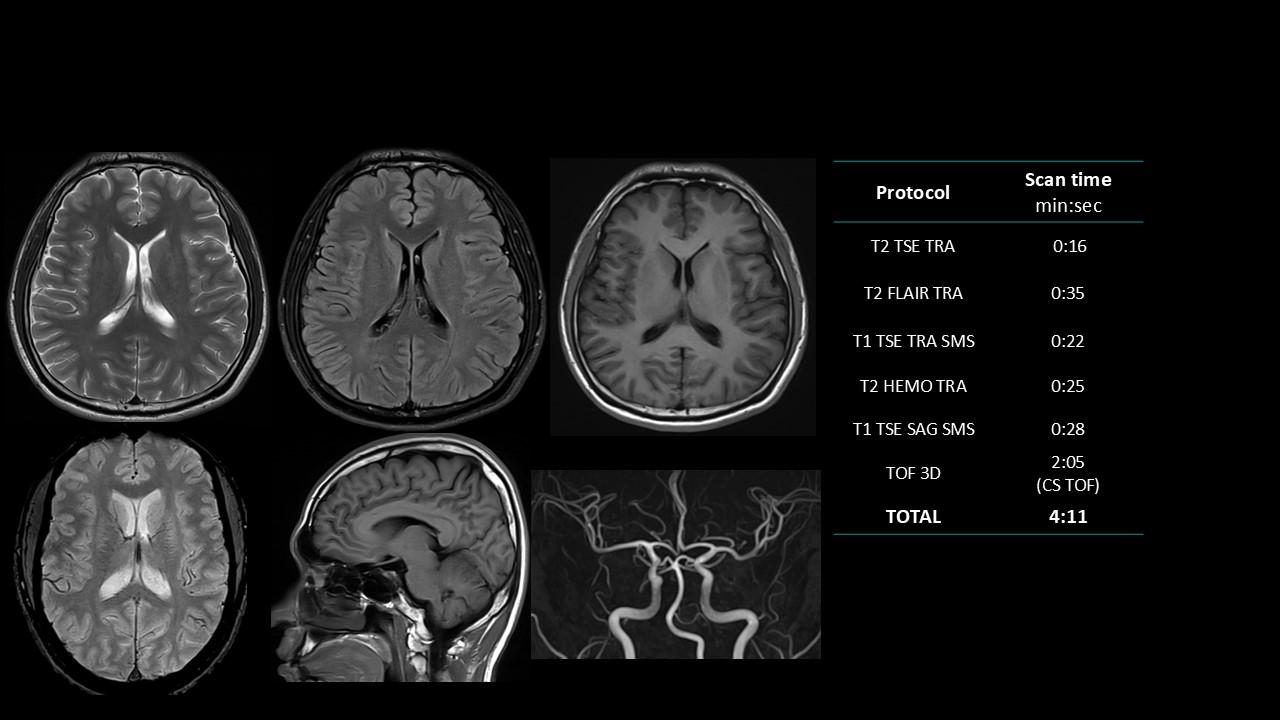

The Deep Resolve protocols are a set of advanced 3T MR imaging protocols designed to achieve high-quality diagnostic imaging with significantly reduced acquisition times.

Enabled by Deep Resolve, the AI-powered image reconstruction technology, these protocols deliver high-quality scans in approximately three minutes across a wide range of anatomical regions.

Developed and meticulously evaluated by Dr. Seong-ho Lee of Leaders Radiology Hospital in Seoul, Korea, the protocols integrate deep learning technology to enhance imaging efficiency while maintaining diagnostic detail.

By reducing scan duration, they improve workflow efficiency and patient experience without compromising image quality.